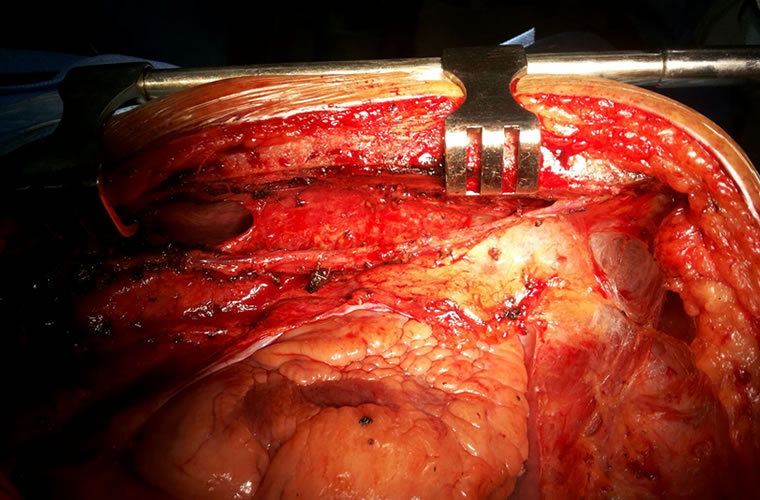

Dr.DineshShanmugaSundaram is specialized himself in each & every part of Cardiovascular & Thoracic Surgery both in Adult & Paediatric or Congenital Heart Diseases. He is both an ethical & academic surgeon,changed the trend in Cardiac Surgery to fast & safe level, as prolonged procedures in Cardiac Surgery increases postoperative complications. We aim at decreasing perioperative complications to the maximal level. Read More